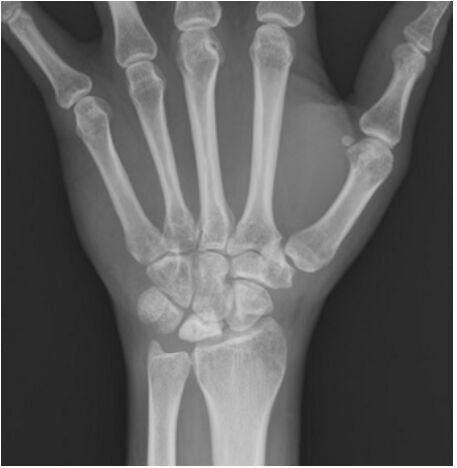

74.34 歲男性長期在風濕免疫科就診,最近開始抱怨左手腕疼痛,醫師告知手腕的月狀骨(lunate bone)有異常。病人的手腕 X 光片影像如圖所示,下列何者最可能造成月狀骨影像之異常?

(A)退化性關節炎(osteoarthritis)

(B)類風濕性關節炎(rheumatoid arthritis)

(C)痛風性關節炎(gouty arthritis)

(D)缺血性壞死(avascular necrosis)